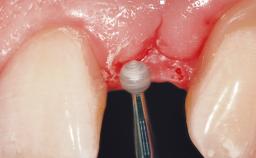

Immediate Placement of an Implant in a Maxillary Left Central Incisor Site

Soft Tissue Grafting Simultaneous

Soft Tissue Contour and Volume Slightly compromised